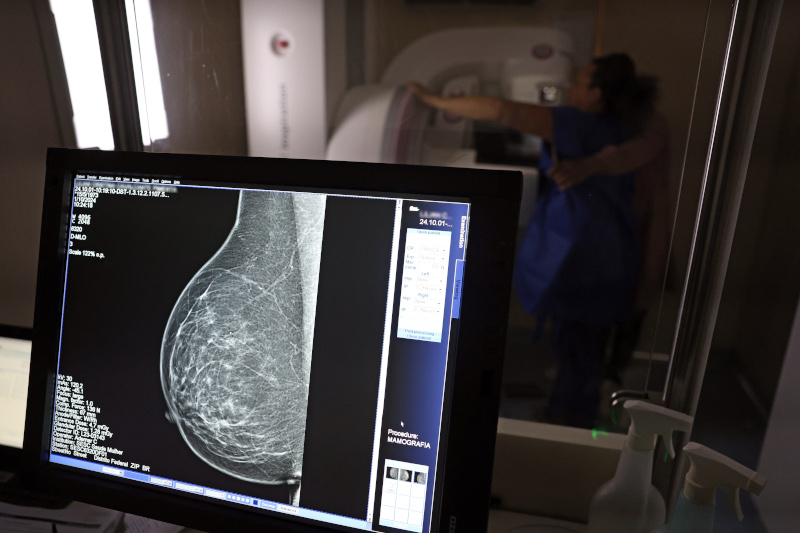

O projeto Controle do Câncer no Estado de São Paulo propõe um modelo de "rastreamento organizado", em que todas as mulheres elegíveis são identificadas, convidadas e individualmente acompanhadas em todas as etapas (imagem: José Cruz/Agência Brasil)